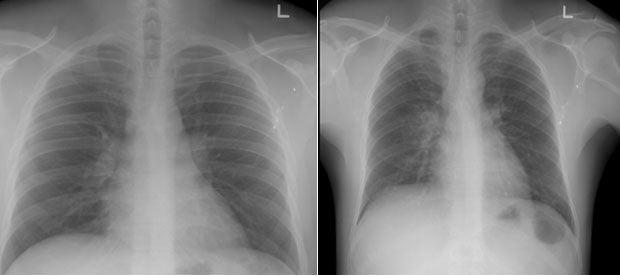

(L) Normal Chest X-Ray  (R) Abnormal Chest X-Ray

The team found that only two per cent of the studied patients, who were asymptomatic or mildly symptomatic, had abnormal chest X-ray readings, which suggested a lung infection. Many of them were monitored at CCF, and only a few were transferred to SGH for further treatment. The remaining 98 per cent had normal chest X-ray readings.

Similar studies in Wuhan and Hong Kong, China, further support the association between severity of condition and the use of chest X-ray. As many as 75 per cent of COVID-19 patients with moderate to severe symptoms in Wuhan, and 70 per cent in Hong Kong, were found to have a lung infection after a chest X-ray.